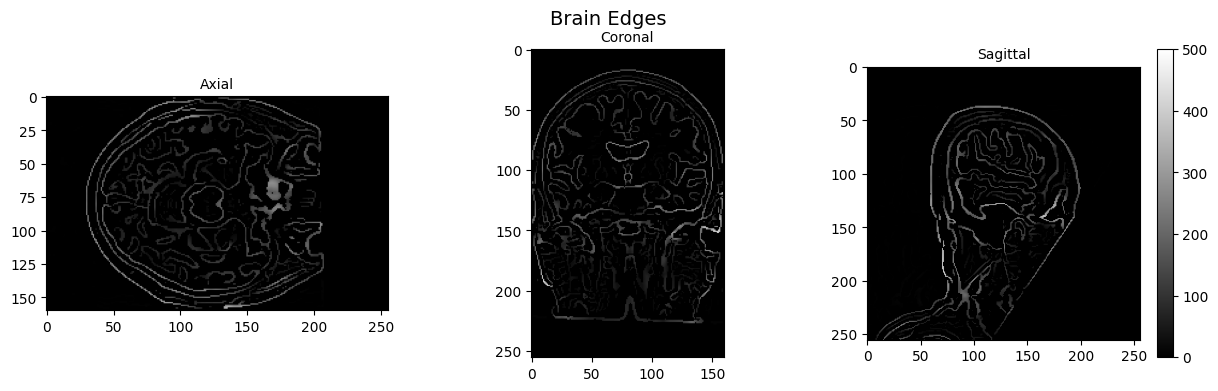

2025-12-22 09:10:32 | INFO | nipype.workflow | [Node] Setting-up "_PlotMosaicNoise0" in "/home/jovyan/Git_repositories/neurodeskedu/books/examples/workflows/MRIQC_workdir/mriqc_wf/funcMRIQC/func_report_wf/fb7ce348b1beef7783adeb055997e4141de31b57/PlotMosaicNoise/mapflow/_PlotMosaicNoise0".

2025-12-22 09:10:32 | INFO | nipype.workflow | [Node] Executing "_PlotMosaicNoise0" <nireports.interfaces.mosaic.PlotMosaic>

2025-12-22 09:10:32 | INFO | nipype.workflow | [Node] Setting-up "mriqc_wf.funcMRIQC.synthstrip_wf.pre_n4" in "/home/jovyan/Git_repositories/neurodeskedu/books/examples/workflows/MRIQC_workdir/mriqc_wf/funcMRIQC/synthstrip_wf/fb7ce348b1beef7783adeb055997e4141de31b57/pre_n4".

2025-12-22 09:10:32 | INFO | nipype.workflow | [Node] Executing "pre_n4" <nipype.interfaces.ants.segmentation.N4BiasFieldCorrection>